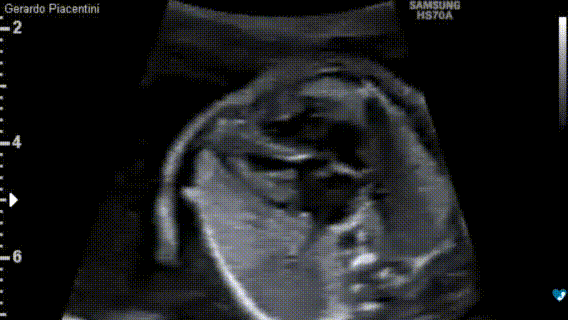

Ecocardiografia fetale - 22 settimane